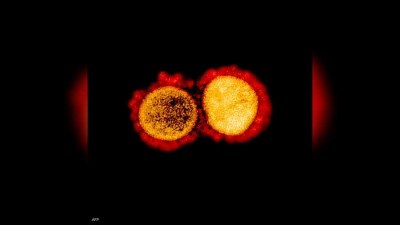

أعلن معهد مستشفى جامعة مرسيليا للأمراض المعدية، الثلاثاء، عن رصد متحور جديد لفيروس كورونا في جنوب فرنسا.

ويحمل المتحور الجديد اسم “B.1640.2″، وسجلت أول حالة إصابة مؤكدة به لدى مسافر عاد من الكاميرون إلى فرنسا قبل نحو شهر

وحسب منظمة الصحة العالمية، فإن عدد المتحورات يزداد بشكل ملحوظ، لكن المتحورات سريعة الانتشار هي التي تشغل العلماء.

وتعد الطفرات سمة مميزة لمعظم أنواع الفيروسات، مما يؤدي إلى ظهور متحورات أو سلالات جديدة منها.

وتثير متحورات كورونا قلق الأطباء، بشأن قدرتها على مقاومة مناعة الجسم الذاتية أو التصدي للقاحات المعروفة.